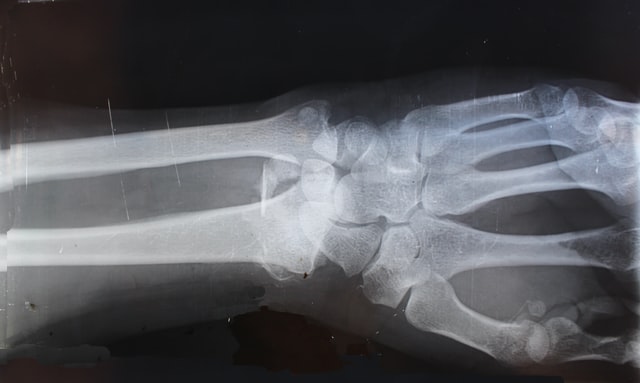

如果當你不幸受傷了,第一個步驟請先掛號骨科或復健科醫生,憑藉超音波和X光去瞭解受傷的位置與類型,再交由運動傷害防護員來接手後續的問題排除。